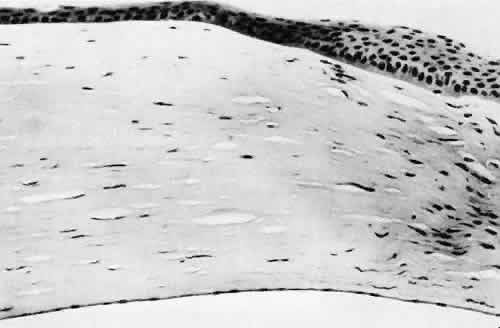

Fig. 11. Light micrograph of a small rent in the capsule of a crystalline lens caused by a needle tip. A small wound such as this may heal leaving only focal opacification. Generalized lens opacification is the more common outcome of crystalline lens capsular damage. (Periodic acid-Schiff stain; × 100.)